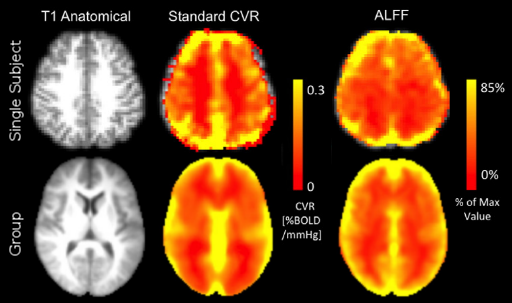

Methods: CVR and lag maps

CVR and lag maps: L-GLM with each lagged regressor and nuisance regressors (12 motion parameters and low frequency trends), voxelwise selection of the lagged model with highest explained variance (R²), normalisation to MNI152 template (2.5 mm isotropic)

Non optimising leads to underestimate the CVR, especially in subcortical areas.

Lag maps show anatomical consistency

Different lag responses, coherent with previous evidence (e.g. Putamen has earlier response than GM)

Results: CVR amplitude maps

Moia et al. 2021 (NeuroImage)

Results: lag maps

Moia et al. 2021 (NeuroImage)